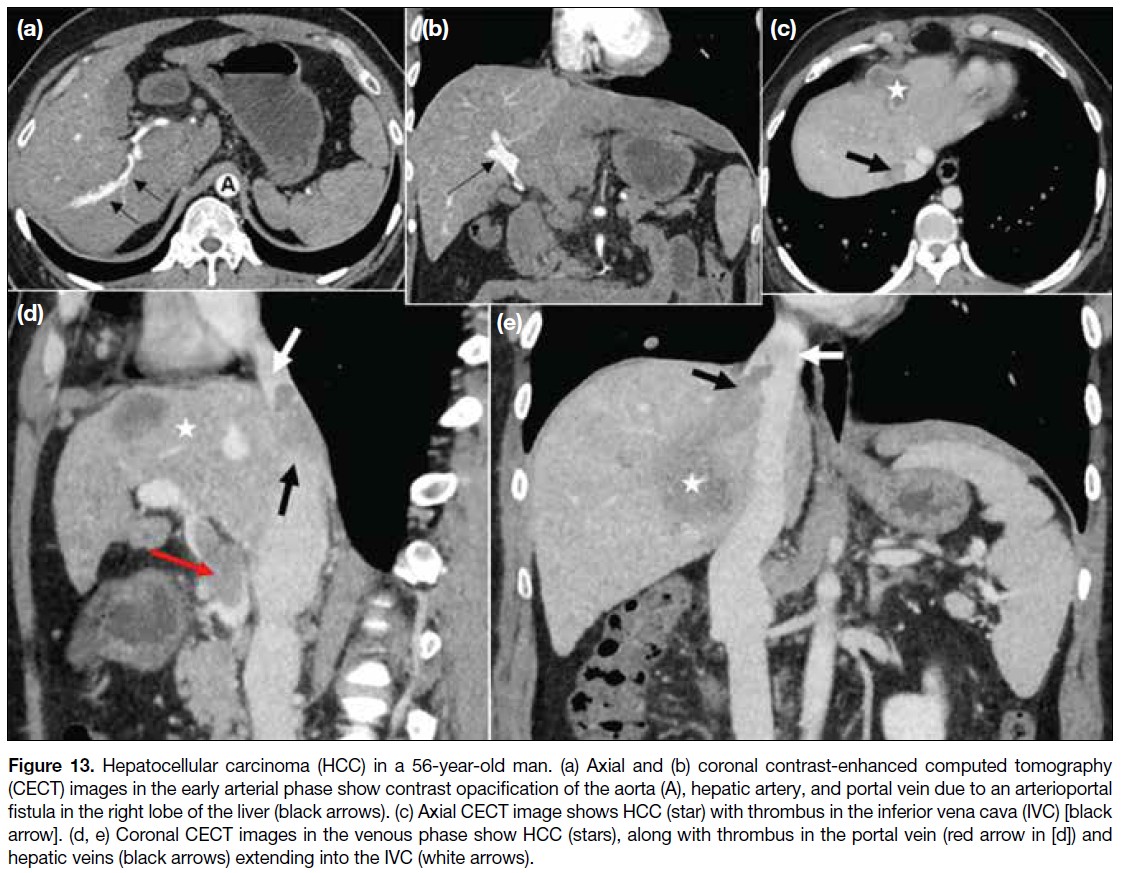

Malignancies most commonly involving the IVC

include those of the liver (4.0%-5.9%), kidney (4%-10%), and adrenal glands (9%-19%).[4] [8] Although the

portal veins are more frequently involved, abnormalities

of the hepatic artery, hepatic veins, and IVC may occur

in hepatocellular carcinomas; accordingly, triphasic

computed tomography should be performed in the

evaluation of liver malignancies (Figure 13).

Figure 13. Hepatocellular carcinoma (HCC) in a 56-year-old man. (a) Axial and (b) coronal contrast-enhanced computed tomography

(CECT) images in the early arterial phase show contrast opacification of the aorta (A), hepatic artery, and portal vein due to an arterioportal

fistula in the right lobe of the liver (black arrows). (c) Axial CECT image shows HCC (star) with thrombus in the inferior vena cava (IVC) [black arrow]. (d, e) Coronal CECT images in the venous phase show HCC (stars), along with thrombus in the portal vein (red arrow in [d]) and

hepatic veins (black arrows) extending into the IVC (white arrows).